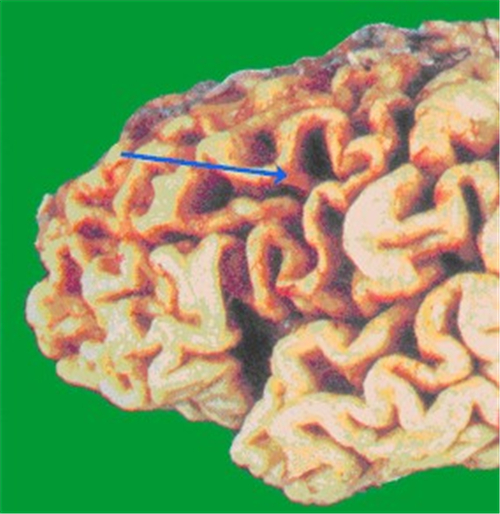

小腦腦萎縮解剖

小腦腦萎縮